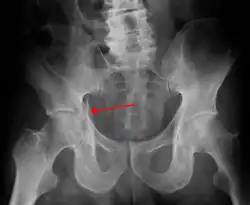

Radiologie standard

De nombreuses incidences radiologiques ont été évaluées par le passé. Une incidence de face du bassin est la première radiographie à réaliser dès l’admission d’un patient pour lequel on suspecte une lésion de l’anneau pelvien. Les radiographies standards révèlent 90 % des fractures du bassin[3].

Différentes incidences obliques sont indiquées en cas de suspicion de fracture du bassin non objectivable sur la radiographie de face. En en cas de suspicion de lésions particulières (fracture isolée du sacrum, fracture du cotyle…) des radiographies spécifiques peuvent être demandées.